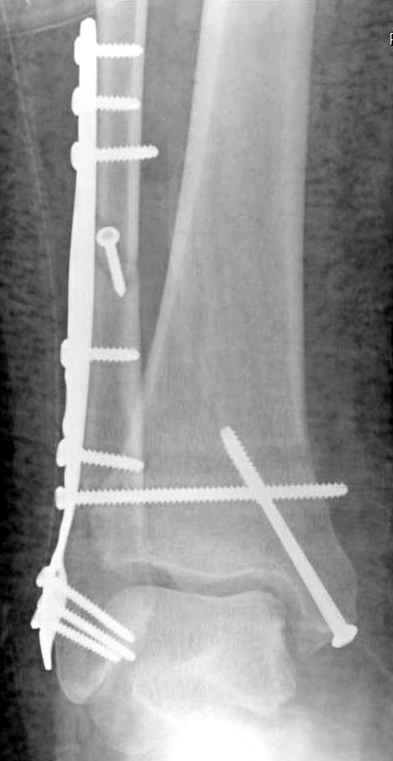

Если до сих ничего не сделано, с артродезом сустава в данный момент я бы повременил, на выставленных январских снимках хорошо сохранившийся сустав, а в "мортиз" (трехчетвертной) и на боковых снимках не менее 5 мм укорочение малоберцовой кости. Косые переломы лучше фиксировать пластинами, как то мы разбирали случай, где было отмечено, что это закон "таранная кость всегда следует за малоберцовой".

В данном случаи я бы уговорил больного на реконструкцию, для этого после удаления шурупов, спереди очистить от рубцов синдесмоз, несросшуюся наружную лодыжку - остеотомия по линии перелома и компрессирующий (lagging technique) кортикальный шуруп 3.5 мм по поперечнику остеотомии. Следующий этап - восстановление длины малоберцовой за счет удлинения, сделать поперечную остеотомию где-то на уровне сантиметр выше вашего синдесмозного шурупа, наложить длинную пластинку, прикрепить пластину за дистальный конец двумя или тремя шурупами; сохраняя контакт пластины с костью, имеющимся

compression&tension device AO system (при отсутствии любой lamina spreader подойдет, создать дистанцию между пластиной и шурупом, проведенным проксимальнее пластины) толкая проксимальный отдел пластины, низвести пластину, мортиз рентгенограмма подскажет на сколько. Если заранее сделать предоперационный план (ренгенограмма другой стороны), тогда точно можно определить, на сколько вам необходимо сделать поперечную остеотомию малоберцовой кости, для закрытия создавшегося дефекта.

Убедившись, что желаемая длина восстановлена, окончательная фиксация пластины, при этом через пластину пару 3.5 мм шурупов на синдесмоз, предпочтительно в четыре кортекса и оставить на 3 мм длиннее, если под нагрузкой синдесмотический шуруп сломается, сломанный конец легче удалить с медиальной стороны.

Медиальная сторона не в нагрузочной зоне, и там большая дыра - если есть 2.7 мм шурупы, или пару спиц в ваших условиях или методика Лазарева. Необходимо уделить внимание к мягким тканям, обнажается кость с латеральной стороны и у места где проводится остеотомия.